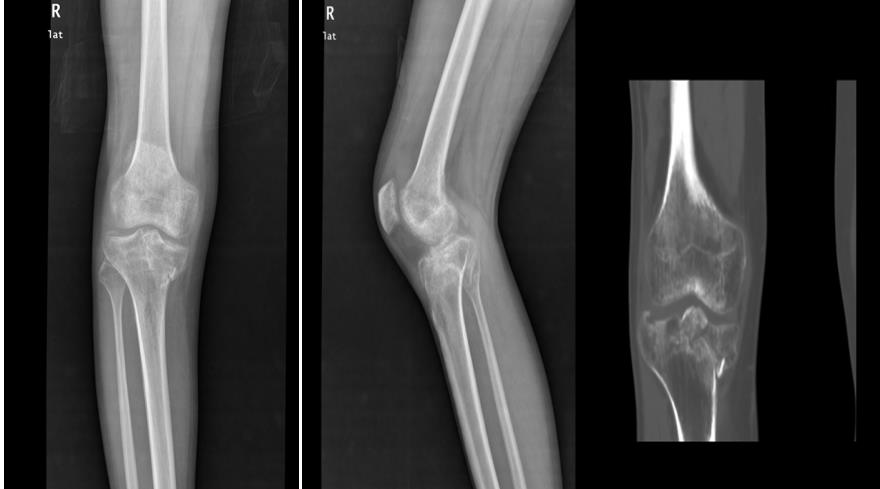

转机出现在亲友的推荐下。罗某抱着一丝希望,跨越三小时路程,从柳州来到玉林市中西医结合骨科医院,慕名求诊于膝关节病与运动损伤科朱博副主任医师。经朱博医师细致检查,确诊为“右胫骨平台陈旧性粉碎性骨折”,骨折端粉碎严重,移位明显,关节面塌陷,且已畸形愈合,手术难度极大。

面对挑战,膝关节病与运动损伤科科主任黄丽雄所带领的膝关节运动与损伤科团队并未退缩,手术团队充分利用医院的3D临床打印中心”。这一创新平台,为罗某实施了个性化术前规划:将膝关节CT扫描数据导入软件,启动建立膝关节模板,使用MultipleSliceEdit模组编辑像素合集,对骨折块进行提取、分割及着色并转换为三维模型。在3D 对象窗口下,观察骨折的塌陷情况、移位距离及旋转角度,使用移动和旋转功能对各个骨块进行移动复位,将虚拟复位前、后的三维模型保存,经3D打印机等比例精准3D打印复制出患者受损的胫骨平台模型。这一技术犹如赋予医生一双“透视眼”,骨折线的走向、碎骨块的位移形态、关节面塌陷的程度等复杂情况在模型上清晰直观、一目了然。

朱博副主任感言:罗先生的病例极具挑战性,胫骨平台粉碎性骨折,属Schatzker Ⅴ型,过伸内翻型胫骨平台双髁骨折,即使新鲜骨折手术难度就较大,加之外伤后3个多月,骨折已畸形愈合,手术难上加难。是三维CT及3D打印技术带来的‘术前透视’能力与团队多年积累的临床经验相结合,才创造了这次成功。我们将持续探索创新技术应用,以更精准、更微创、更高效的方式,守护每一位骨伤患者重新站立的权利。